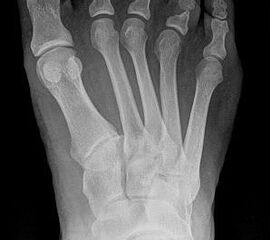

• Vorfuß in fixierter Plantarflexion aller Zehen- und Mittelfußstrahlen (direkter Hohlfuß, Pes cavus) (Abb. 3)

Direkter Hohlfuß (Pes cavus)

• Druckdolenz unter allen Metatarsaleköpfen

• Druckdolenzen über den proximalen Interphalangealgelenken der Kleinzehen

Biomechanische Überlegungen zum direkten Hohlfuß

Der direkte Hohlfuß zeigt im gesamten Vorfuß durch die steilgestellten Metatarsalia I-V nicht nur eine Betonung der Vorfuß-Equinusstellung mit schmerzhafter plantarer Beschwielung aller Metatarsaliaköpfe, sondern auch eine transversale Verbreiterung (Spreizung) der distalen Metatarsalia und Phalangen. Eine Inversion des Rückfußes kann durch zusätzliche Dysbalancen gelegentlich konsekutiv entstehen.

Da der balancierende Effekt der intrinsischen Muskulatur ausbleibt, welcher die Grundphalangen plantarflektieren würde, zieht die übermächtige extrinsische Muskulatur (M. extensor digitorum longus) infolge ihrer Ansätze an den Endphalangen die Grundphalangen in die ungehinderte Hyperdorsalextension. Wie eine Ziehharmonika wird der Vorfuß dem Rückfuß angenähert (Abb. 20). Es bildet sich eine Klauenzehendeformität. Die Metatarsaleköpfe werden in die Plantarflexion „geschoben“. Der Drehpunkt der Bewegungsachse der Grundgelenke verschiebt sich nach plantar und selbst die langen Flexoren (M. flexor digitorum longus) fungieren als Dorsalextensoren des Grundgliedes und verstärken die Deformität.

Die verstärkte Aufspreizung des Vorfußes resultiert ebenfalls aus der Schwächung der intrinsischen Muskulatur, welche in normaler Funktion auch eine transversale Verspannung der distalen Metatarsalia bewirkt. Die intermetatarsal verlaufenden Anteile der M. interossei ermöglichen eine aktive Verspannung zwischen den einzelnen Metatarsalia.

Durch Schwächung der intrinsischen Grundgliedflexoren entstehen flexible, später kontrakte Klauenzehen.